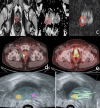

Gallium-68 (68Ga)-prostate-specific membrane antigen (PSMA) positron emission tomography/computed tomography (PET/CT) is a relatively new imaging modality that has already proved its role in the initial staging of prostate cancer and in biochemical recurrence following definitive primary therapy. Furthermore, emerging data several ongoing studies demonstrate its potential role in the primary diagnosis of this malignancy. We present a 67-year-old male patient with increasing clinical suspicion of prostate cancer despite a previous negative prostate gland biopsy. He was referred to our nuclear medicine department for a 68Ga-PSMA PET/CT with the aim of improving tumor localization and assisting in the guidance of repeat prostate biopsy. One month before presentation of elevated prostate-specific antigen levels, he underwent multiparametric magnetic resonance imaging (mpMRI), which revealed a prostate imaging reporting and data system 4 lesion in the right lobe of the prostate gland. The MRI lesion completely matched a PRIMARY score 5 lesion registered by PET/CT. Furthermore, we detected another suspicious finding in the left lobe (PRIMARY score 4). The patient underwent PSMA PET/CT-guided MRI/ultrasonography fusion transperineal biopsy of both lesions. The latter were histologically confirmed as prostate carcinoma with a Gleason score of 3+4 =7.